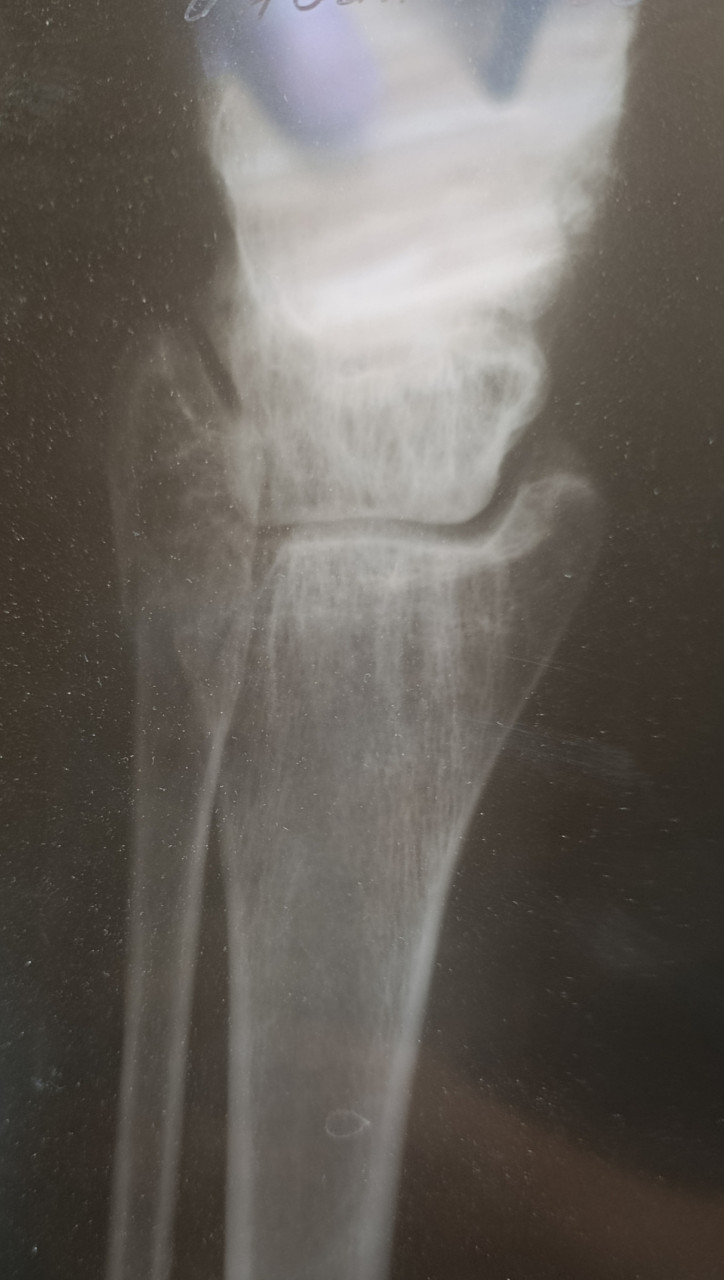

Здравствуйте. У меня перелом, а вот чего именно врач не сказал. Кости или самой лодыжки? Наложили гипс, но он очень стал давить. Пришла на прием к травматологу и его сняли с болью, просто ужас. И отправили домой, вообще без ничего. Сказали купите ортез и носите. Оденете дома. Я на костылях пропрыгала почти 2 суток в эластичном бинте. Скажите пожалуйста, снятие гипса не может повлечь за собой дальнейшее смещение и перелом именно какой части у меня? Спасибо

Здравствуйте. На этом рентгеновском снимке изображение получилось не очень чётким из-за бликов и неравномерного освещения и как я понимаю красное это ноготь, но перелома или выраженной трещины на видимых участках костей я не вижу. Однако для точной оценки нужны как минимум две проекции и осмотр врачом-травматологом. По одному фото плохого качества окончательный вывод сделать нельзя.

Здравствуйте, Владимир Геннадьевич, я поменяла фото в вопросе. Не могли б вы взглянуть ещё раз. Спасибо